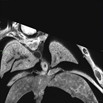

| EFIC imaging of mutant 012-029-NB (E16.5) reveals DORV, right aortic arch, VSD, AVSD, and stenotic pulmonary artery (PA) | Cplane1b2b012Clo/Cplane1b2b012Clo | C57BL/6J-Cplane1b2b012Clo |

| Serial 2D EFIC image stack of mutant 012-029-NB in the coronal view reveals DORV, subaortic VSD, hypoplastic PA, common AV valve, and right aortic arch

Click thumbnail to play movie. | Cplane1b2b012Clo/Cplane1b2b012Clo | C57BL/6J-Cplane1b2b012Clo |